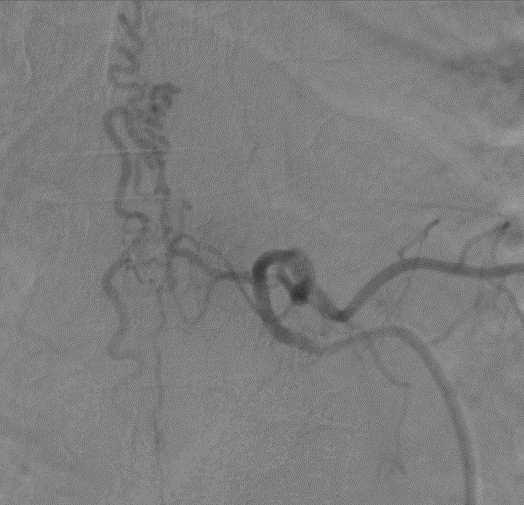

Theo các bác sĩ tại Hoàn Mỹ Sài Gòn nhận định, đây là trường hợp có khả năng tổn thương tủy ngực dẫn đến yếu 2 chân và rối loạn tiểu tiện. Ông S. được chỉ định chụp MRI cột sống ngực, kết quả cho thấy người bệnh bị dị dạng mạch máu tủy ngực gây nên biến chứng phù tủy. Đồng thời, hình ảnh chụp DSA mạch máu tủy cho thấy hình ảnh ổ dị dạng mạch máu tủy ngực ngang mức D7-D8, được cấp máu bởi động mạnh màng cứng tủy cùng mức, với tĩnh mạch dẫn lưu giãn ngoằn nghèo kéo dài từ D5-D9.

Sau khi xác định nguyên nhân chính xác gây nên tình trạng yếu chân của ông S. các bác sĩ đã ngay lập tức thực hiện can thiệp tắc dị dạng bằng kỹ thuật đưa ống thông siêu nhỏ, tiếp cận ổ dị dạng và bơm keo sinh học để tắc ổ dị dạng. Chỉ sau khoảng 1 tiếng can thiệp, bác sĩ đã can thiệp tắc ổ dị dạng thành công, bảo tổn được các mạch máu tủy quan trọng cho người bệnh.

Hình ảnh DSA trước và sau khi can thiệp tắc dị dạng thành công

Sau can thiệp, ông S. phục hồi nhanh chóng, ông đã có thể tự kiểm soát được vấn đề đại tiểu tiện, không còn mất kiểm soát như trước. Tình trạng yếu chân đã cải thiện hơn, có thể đứng, đi lại nhẹ nhàng và xuất viện sau 2 ngày can thiệp. Ông S sẽ tiếp tục tập vật lý trị liệu phục hồi chức năng tại nhà và tái khám theo dõi định kỳ theo lịch hẹn của bác sĩ.